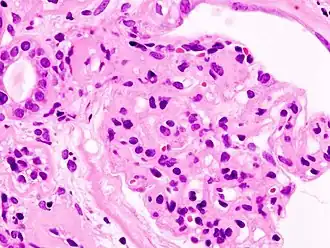

| Imagem microscópica da glomeruloesclerose diabética, principal causa da síndrome nefrótica em adultos | |